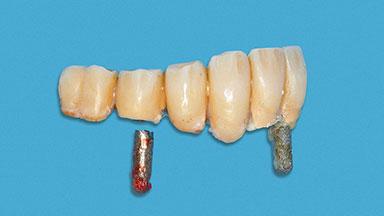

A 93-year-old female patient presented in September 2010 with an enlarged swelling on the lingual side of her lower incisors. At the time, she was essentially healthy, except for reduced vision due to bilateral age-related macular degeneration. She had been a heavy smoker (about 30 cigarettes a day) for the past 20 years after becoming a widow. The patient lived at home by herself, with full-time domestic support. An extraoral examination revealed nothing adverse. Intraoral plaque control was anything but ideal, and a soft-tissue tumescence was visible around the lingual aspect of 41–42. Because the nature of the lesion was not clear, a biopsy was carried out that revealed the inflammatory nature of the lesion. The panoramic radiograph showed six irregularly distributed mandibular implants supporting a full-arch prosthesis, with various degrees of interproximal peri-implant resorption. The periapical radiograph revealed interproximal bone resorption mesially and distally to implant 41.